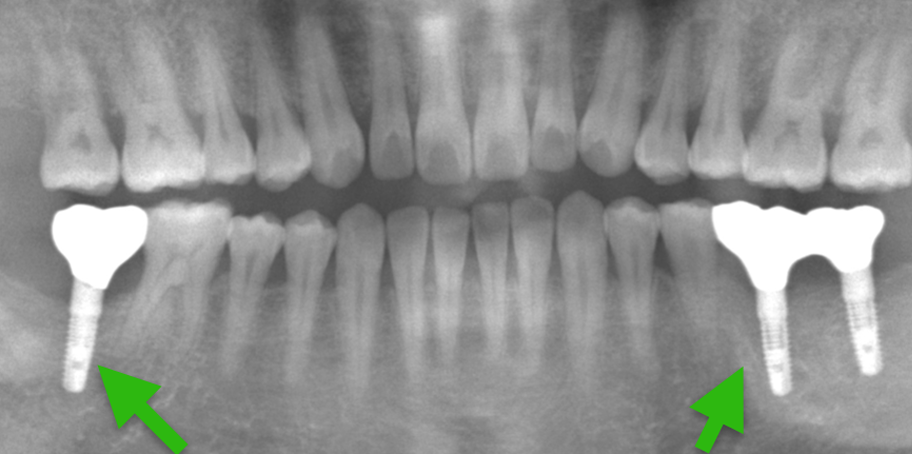

Case11.

| 主 訴 | 下の奥歯で噛めない、もっと美味しく食事をしたい |

| 治療期間 | 約6ヶ月 |

| 治療費 | 1,100,000円(税込) |

| 治療内容 | 残すことが難しい歯を抜歯し、 インプラント治療を行いました。 |

| 治療のリスク | インプラント治療は外科処置を伴うために、 治療後に腫れ、痛みが出ることがあります。 セラミックは稀にかける場合があります。 |